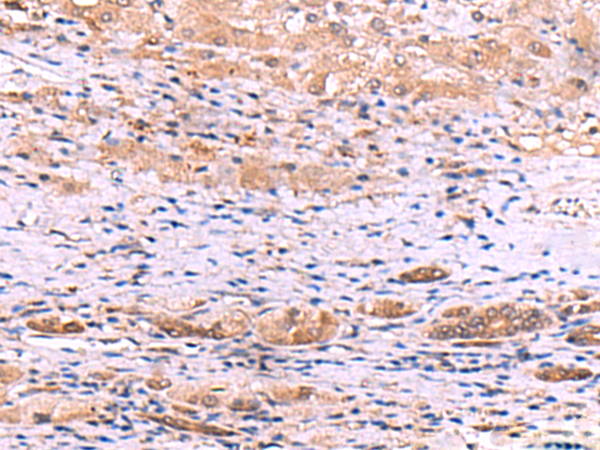

IHC positive control:

Human liver cancer

ELISA, IHC